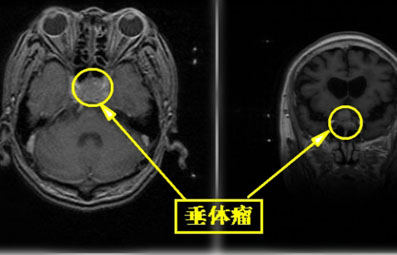

垂体瘤,畸形,在你的开发生长脑垂体 -具备几种症状。这些症状通常逐渐发展,但较终可能导致其他内分泌失调,例如库欣氏病和肢端肥大症。

大多数垂体瘤很小。这些被称为微腺瘤。但是,较大的肿瘤(称为大腺瘤)会向垂体和周围组织施加压力,并导致视力发生变化,例如复视和周围视力丧失。